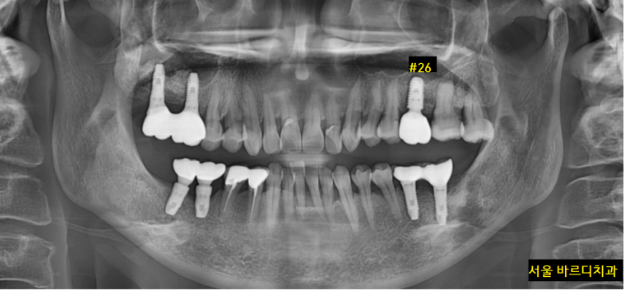

231120

미사역 임플란트 식립 후 5개월이 지나

보철을 완성한 사진입니다.

발치 후 3개월

뼈이식 후 5개월

8개월이 지나 진료가 끝났습니다.

결코 짧은 시간이 아니죠~?